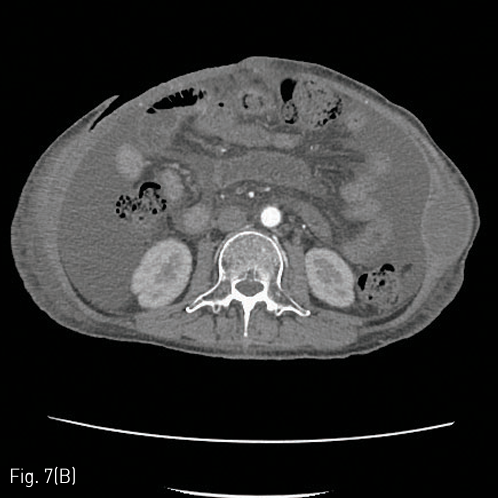

이후 환자는 복벽 혈종 및 피부 결손에 대해 괴사조직제거술을 시행하고 성형외과적 피판성형술 계획 및 보존적 치료하였으며 (Fig. 7A, 7B), 증상재발 없이 경과 관찰중이었으나, 입원 109일째 전신상태 및 폐렴 합병증의 악화로 사망하였다

Fig 7B

(B) A skin defect could be observed in the anterior abdominal wall in the abdominal CT taken on day 52 from the initial embolization therapy with all hematomas of the abdominal wall removed and no recurrent bleeding.